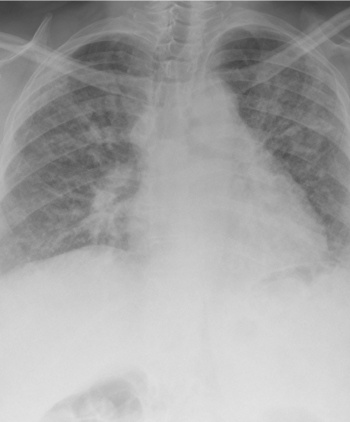

Severe pulmonary fibrosis

Severe pulmonary fibrosis(click to enlarge)